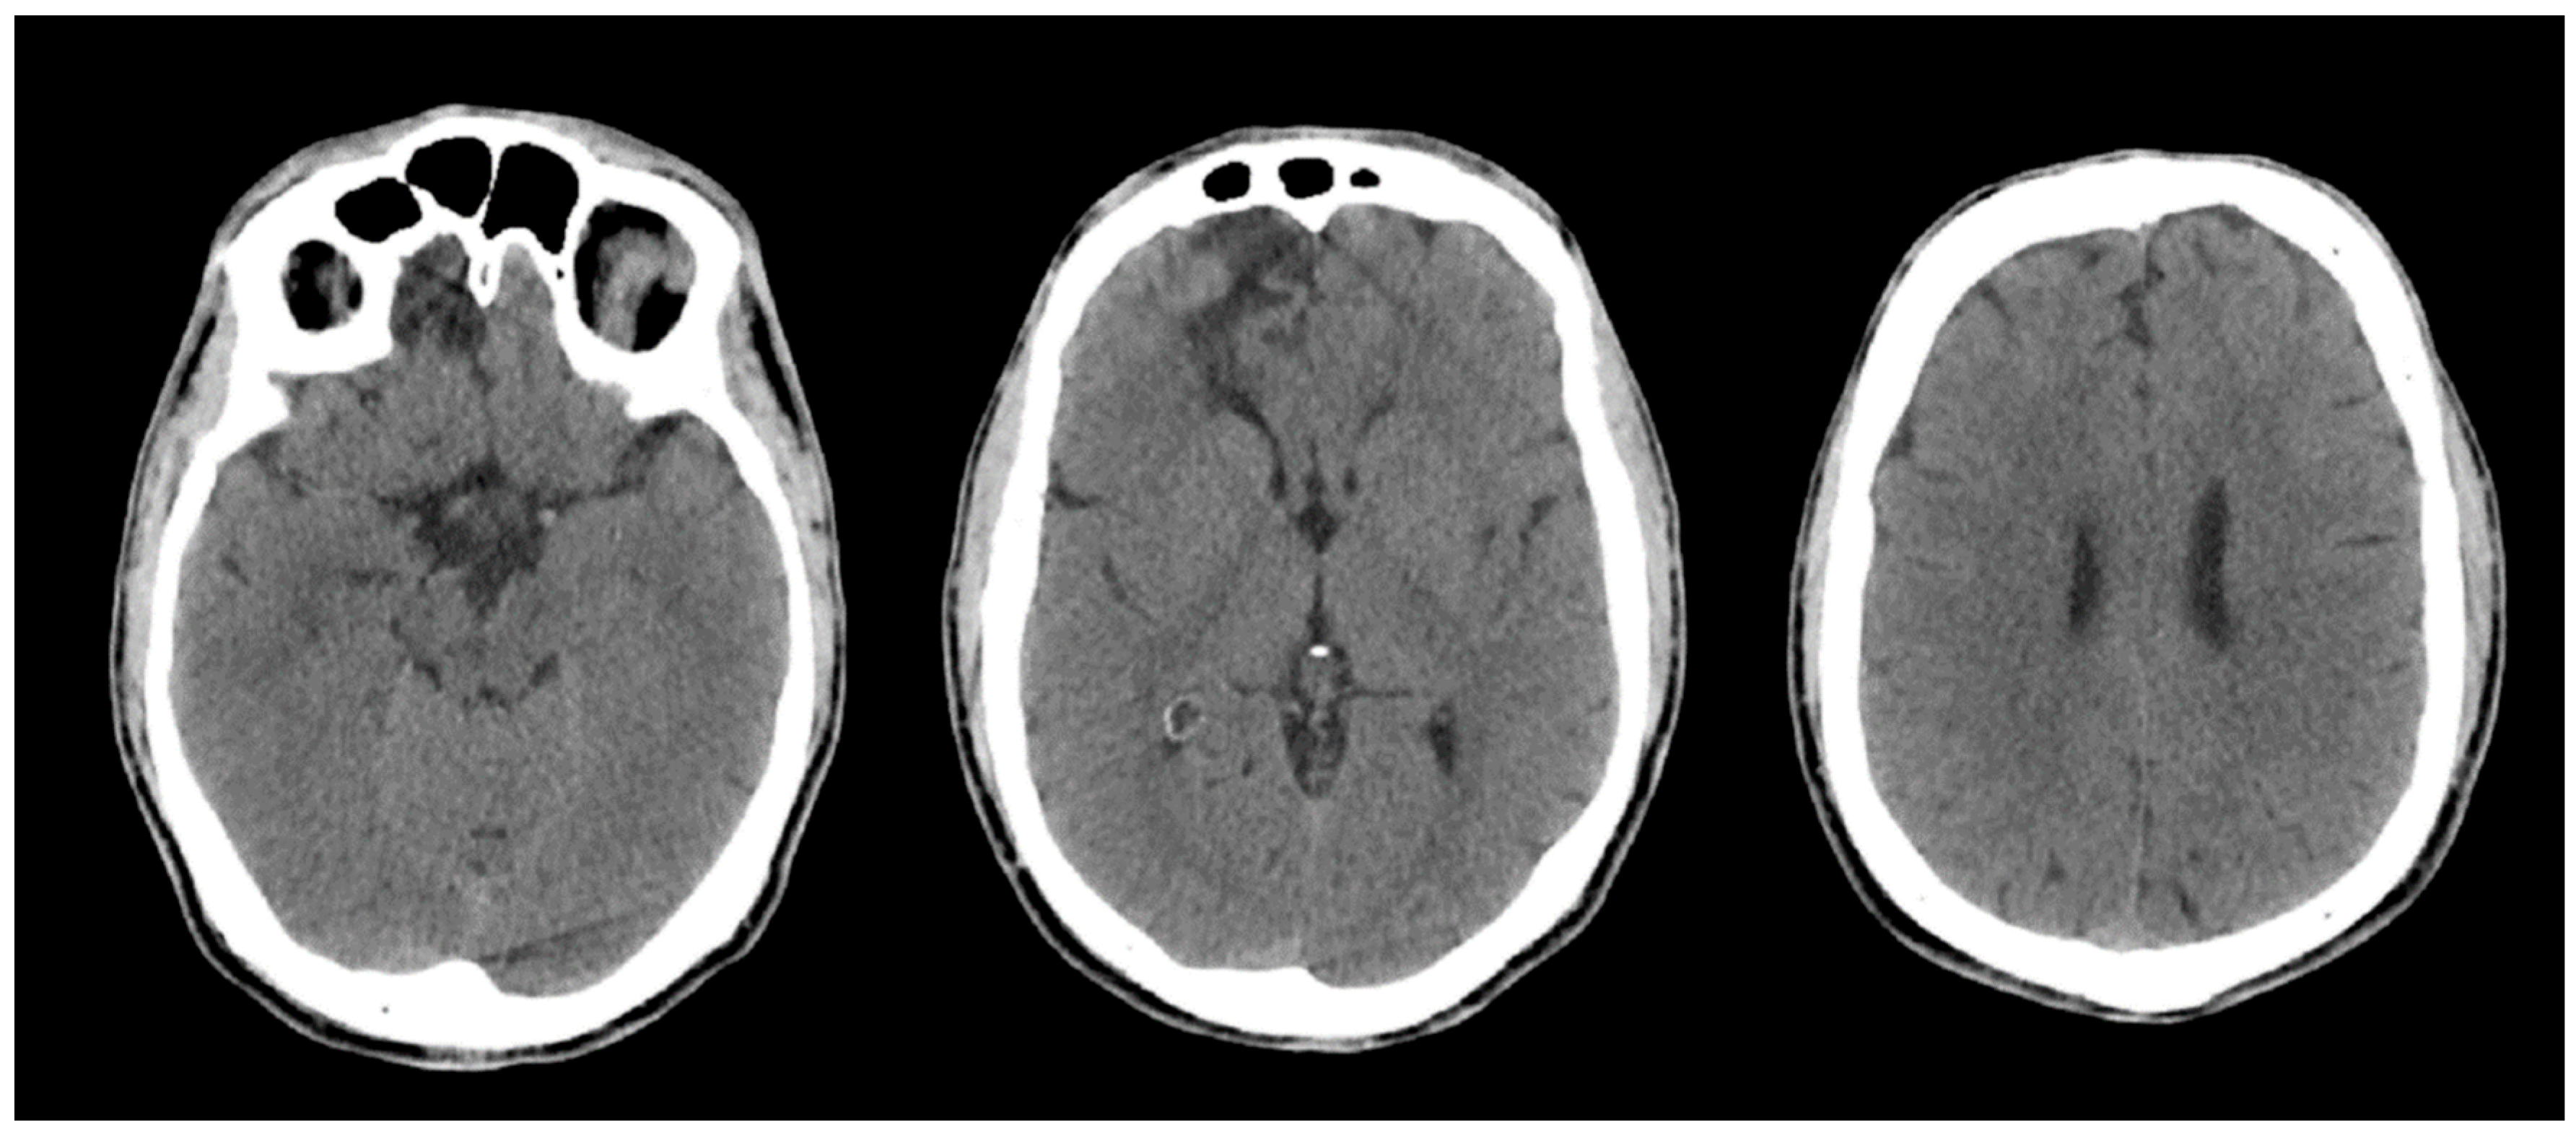

Brain CT performed on admission and repeated on hospital day 2 showed no intracranial haemorrhage or acute focal or global ischaemia, and no intracranial arterial occlusion without interval change. The known right frontal hypodensity, consistent with chronic gliosis following prior head trauma, was identified (Figure 2). Brain MRI performed during the admission was significantly limited by motion artefacts; therefore, no additional diagnostic information could be obtained.

Figure 2. Non-contrast brain CT performed on admission following out-of-hospital cardiac arrest. Representative axial slices demonstrate preserved grey–white matter differentiation, including at the level of the basal ganglia, with no evidence of acute intracranial haemorrhage, mass effect, or diffuse cerebral oedema. A focal right frontal hypodensity consistent with chronic gliosis related to prior head trauma is noted.